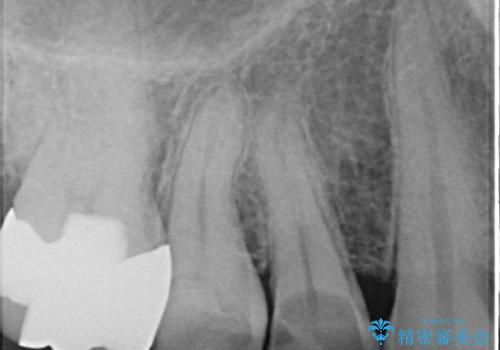

- 食事中に歯が欠けてしまった事を主訴に来院された患者様です。

小臼歯が広範囲に欠けてしまっています。

部分的な詰め物では再びかけてしまうリスクが高いため、オールセラミッククランにて補綴治療をすることとしました。